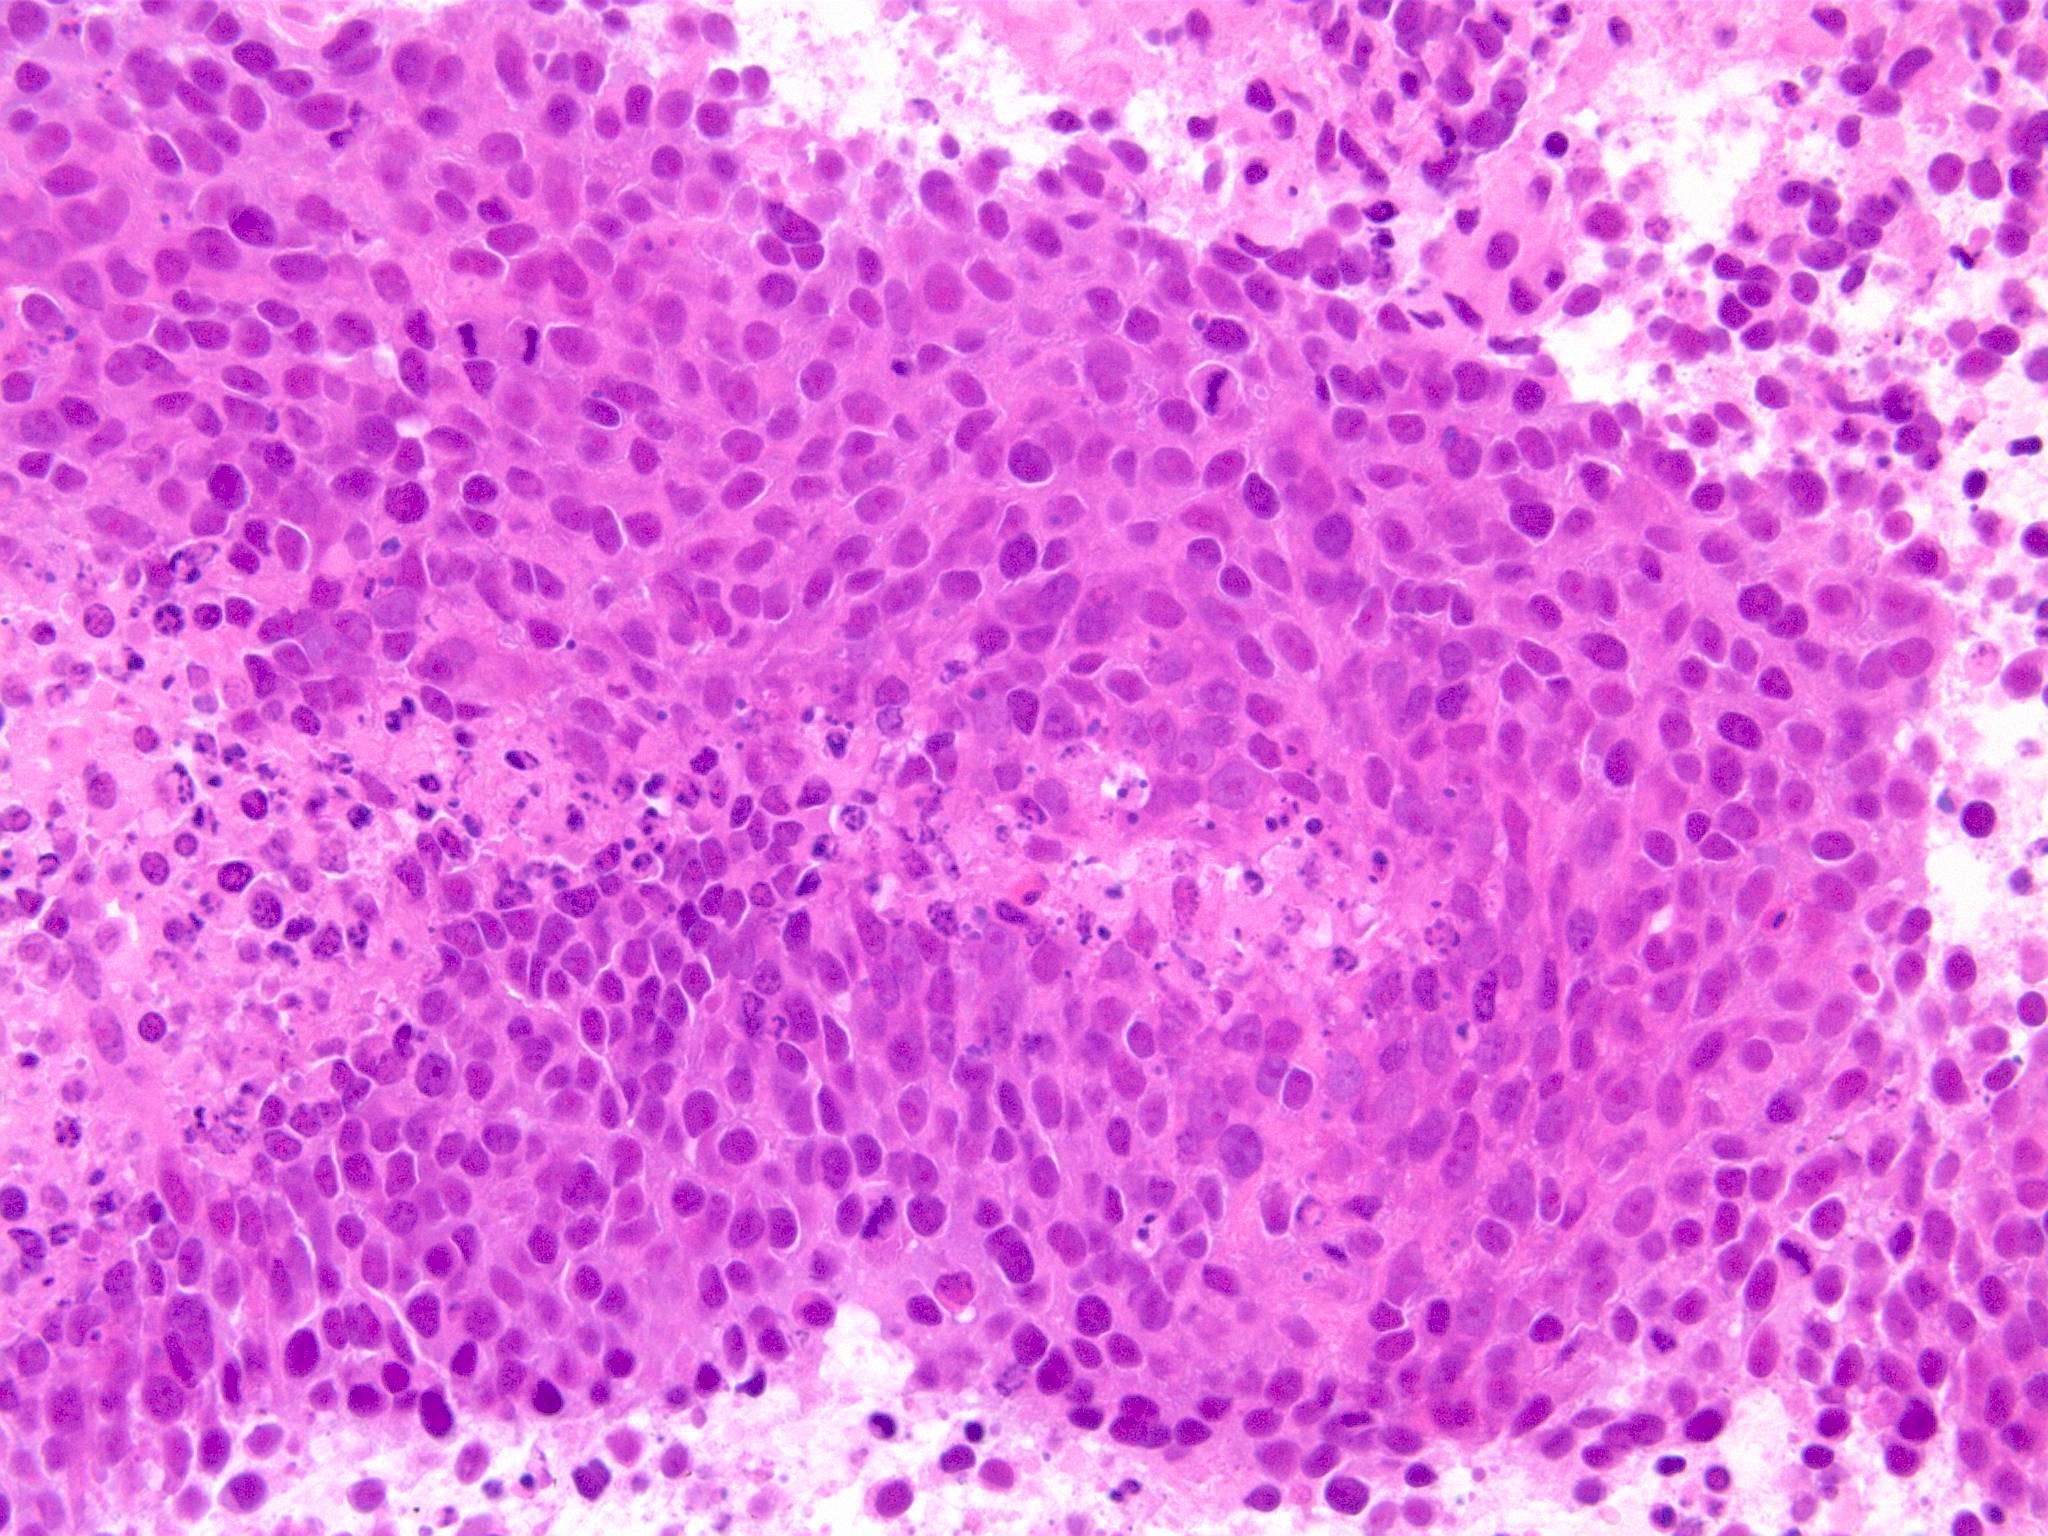

副鼻腔腫瘤生検組織

日本病理学会中部支部交見会のスライドより。(S.Suzuki Dr.)

NUT03.jpg NUT04.jpg

詳細は以下のcase reportをご参照ください。

Suzuki S, Kurabe N, Minato H, Ohkubo A, Ohnishi I, Tanioka F, Sugimura H.

A rare Japanese case with a NUT midline carcinoma in the nasal cavity: a case report with immunohistochemical and genetic analyses. Pathol Res Pract. 2014 Jun;210(6):383-8. doi: 10.1016/j.prp.2014.01.013. Epub 2014 Feb 22. PMID:24655834